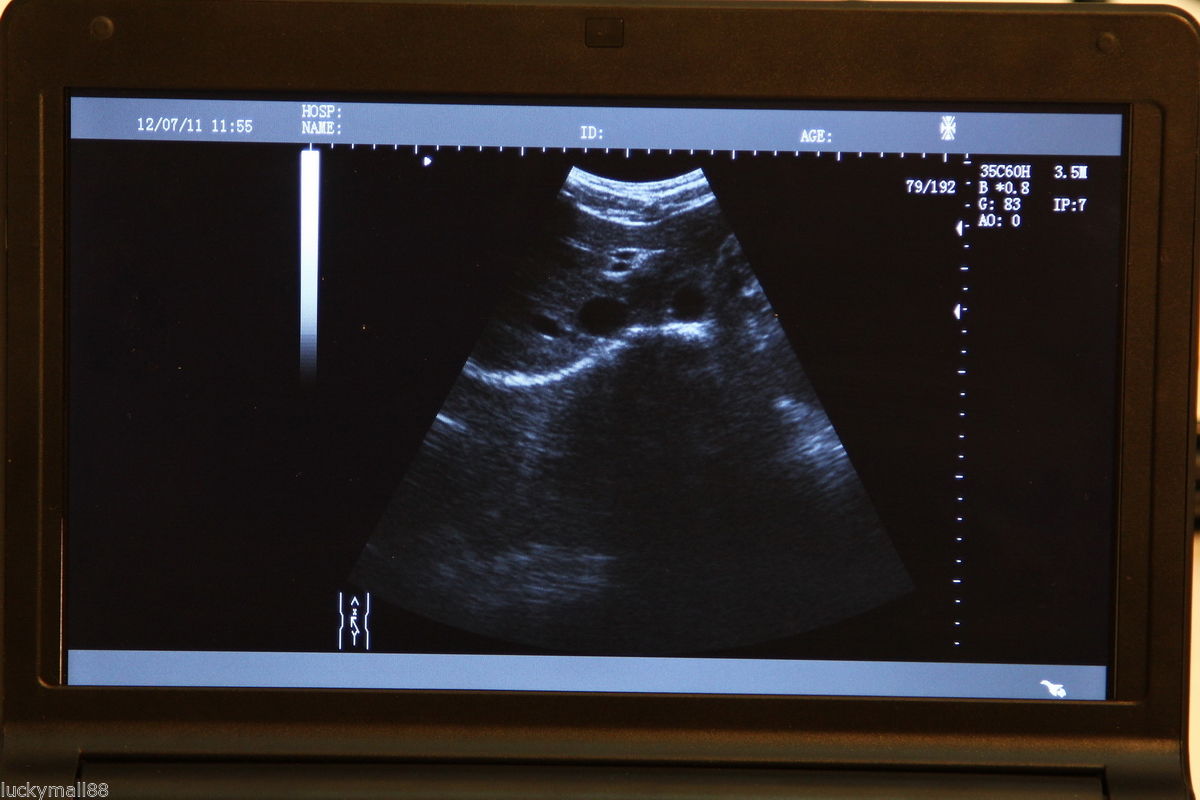

Our portable ultrasound scanner is equipped with cutting-edge technology that improves diagnostic accuracy. With its convex linear transvaginal probe, it allows for detailed imaging of internal structures. The tool is designed to be user-friendly, meaning healthcare professionals can easily operate it without extensive training. Therefore, its advanced features can help in making quick and informed decisions in clinical settings, which is essential for patient care.

This portable ultrasound scanner is particularly beneficial in obstetrics and gynecology, as it provides clear and detailed images necessary for monitoring pregnancies and diagnosing conditions. Its transvaginal probe allows for a closer view of reproductive organs, which helps in identifying issues early on. Consequently, this versatility ensures that healthcare professionals can use it in various procedures, making it an essential tool in women’s health.